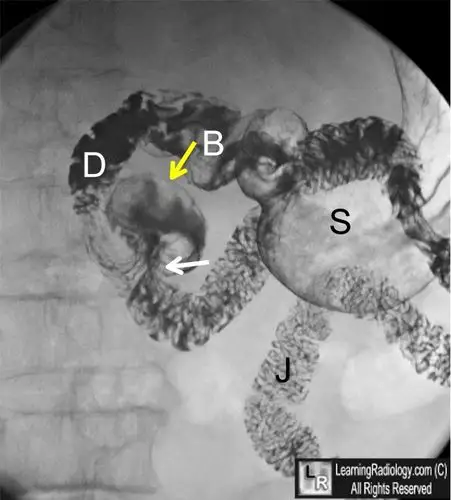

图文并茂,一文了解十二指肠憩室! | 以影识病